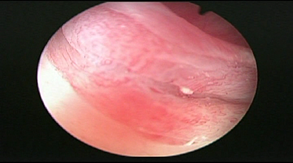

The vaginal image prior to treatment shows a vaginal fundus with a large ulcer with telangiectasias and mucositis (Image 3), and after the 4th treatment a vagina is found with frank reduction in the size of the ulcer, mucositis in resolution and absence of telangiectasias (Image 4).

Image 3 Vagina prior treatment.

Image 4 Vagina after fourth treatment.